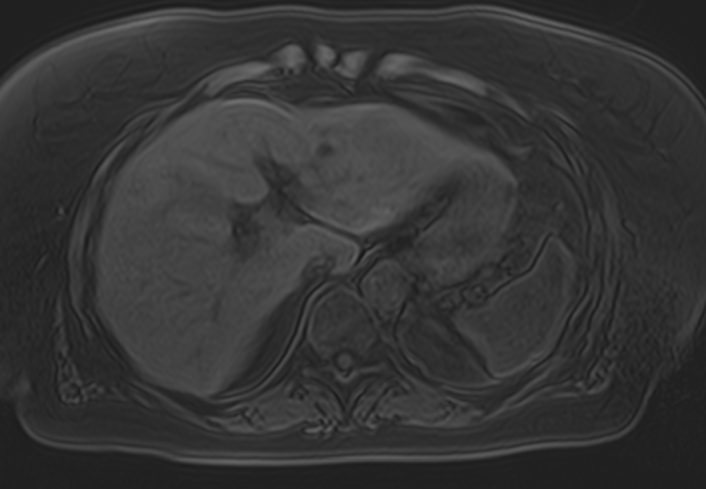

В клинике «Доступная медицина» МР томография проводится на новейшем высокопольном томографе экспертного класса TOSHIBA VANTAGE TITAN 1,5 Тесла. Высокая индукция магнитного поля обеспечивает повышенную четкость изображений при проведении обзорной МРТ брюшной полости, что гарантирует точность и эффективность диагностики заболеваний печени, желчного пузыря, поджелудочной железы и селезенки. Аппарат послойно сканирует исследуемую область с шагом от 1 мм в различных плоскостях, затем трансформирует результаты в трехмерные изображения превосходного качества. Для уточнения характера патологических изменений одного из органов назначается прицельная МР томография данного органа.

Для расширения возможностей диагностики, при необходимости уточнения характера патологических изменений применяется контрастное усиление. Для этого в вену вводится контрастный препарат, содержащий металл гадолиний (Магневист, Гадовист и др). Препарат фиксируется в очагах поражения, позволяя диагностировать их при минимальных размерах, что бывает особенно важно в диагностике опухолей.

- Доброкачественные образования (кисты, гемангиомы) и злокачественные опухоли органов брюшной полости (первичные опухолевые очаги и метастатические поражения, в том числе, брюшины).

- Заболевания печени (жировая инфильтрация печени, гепатиты, цирроз и др).

- Заболевания желчного пузыря и желчевыводящих протоков, поджелудочной железы (желчекаменная болезнь, холецистит, панкреатит и др).